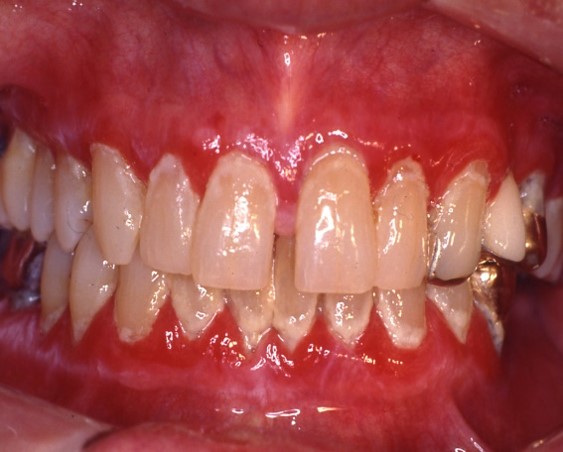

Figure 1 & 2: Lichen planus occurring on the gingiva (desquamative gingivitis) and tongue (plaque-like form).

Figure 3-5: Mucous membrane pemphigoid (MMP) presenting as desquamative gingivitis; poor plaque control resulting from the inability to brush comfortably; patient responded well to topical steroids applied in delivery trays.

Mucous membrane pemphigoid (MMP) is an autoimmune blistering disorder that affects the oral &/or other mucosal surfaces. It affects women twice as often as men and occurs most frequently in the 5th to 7th decades of life.2 Clinically, MMP presents as desquamative gingivitis (bright red gingiva) often showing a positive Nikolsky’s sign (sloughing of the outer surface of the oral mucosa with slight rubbing). (Figures 3-5)